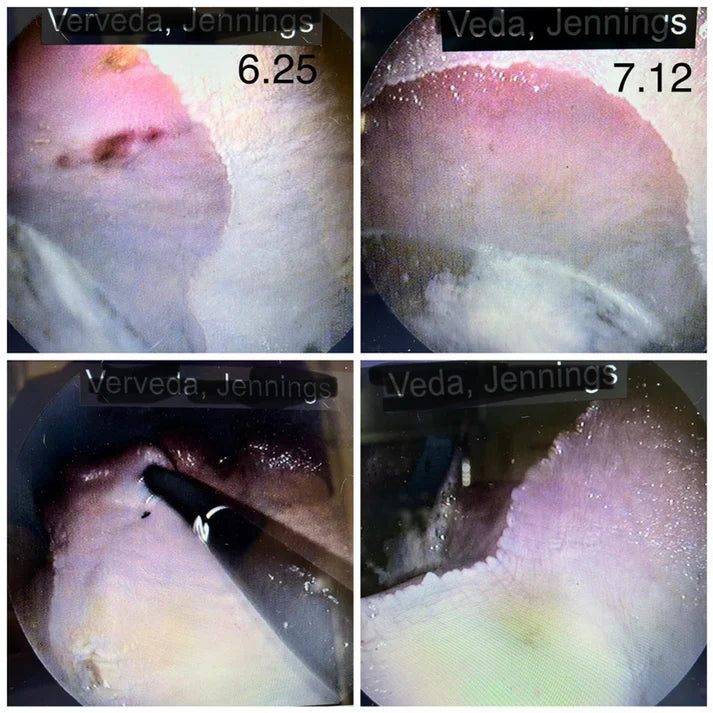

Unlike other formulas Vet Zone does not alter the ph of the stomach thereby eliminating the rebound acidification. ** Once medications that change the ph of the stomach are stopped the animal is at an increased risk of gastric ulceration.

On average the amount of time needed in our case studies to get an animal that is not eating to back on full feed is 3 days

- On average the amount of time needed in our case studies to heal gastric ulcers 30 days